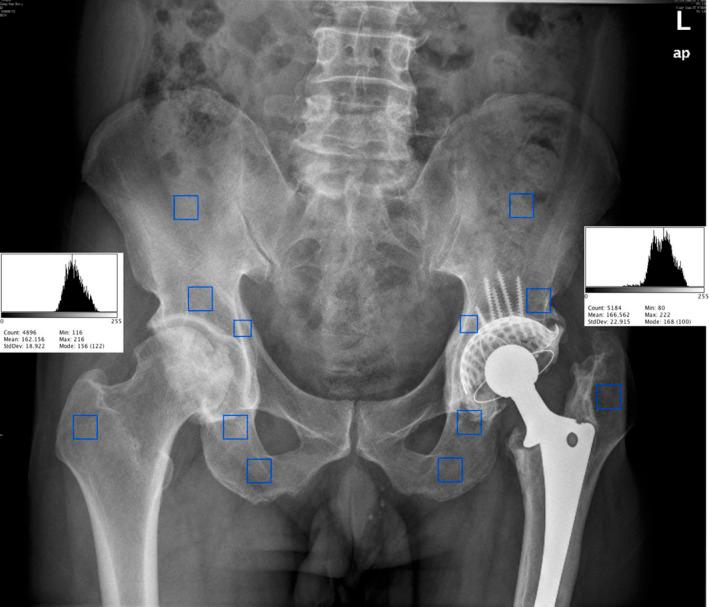

髋关节翻修术中应用嵌压植骨联合钛网重建髋臼骨缺损:回顾性迷你研究。

Impaction Bone Grafting Combined with Titanium Mesh for Acetabular Bone Defects Reconstruction in Total Hip Arthroplasty Revision: A Retrospective and Mini-Review Study.

To investigate the application of impaction bone grafting (IBG) combined with Ti-alloy mesh for acetabular bone defect reconstruction in total hip arthroplasty (THA) revision and follow up the clinical outcomes and imaging findings.

METHODS

The clinical and imaging data of patients who were admitted to our hospital from January 2000 to December 2020 and underwent acetabular bone defects reconstruction using IBG combined with titanium mesh were retrospectively analyzed. Preoperative and post-revision Oxford and Harris scores, and post-revision complications were evaluated. Radiographs were used to determine center of rotation (COR) of the hip joint, transparency line, bone graft fusion, and bone mineral density (BMD) around the hip joint.

RESULTS

Significant improvement was observed in both Oxford and Harris scores (P < 0.05). The radiographs taken at the last follow-up examination showed no significant differences in the acetabulum COR, offsets, inclination angle, mean ratio of vertical value, and BMD analysis between the post-revision side and contralateral side (P > 0.05). The follow-up data showed restoration of the mesh implant and graft bone fusion.

CONCLUSIONS

The application of IBG combined with titanium-alloy mesh in revision THA patients with acetabular defects was found to provide satisfactory outcomes. However, large-scale studies are still needed to further elucidate the long-term outcomes.